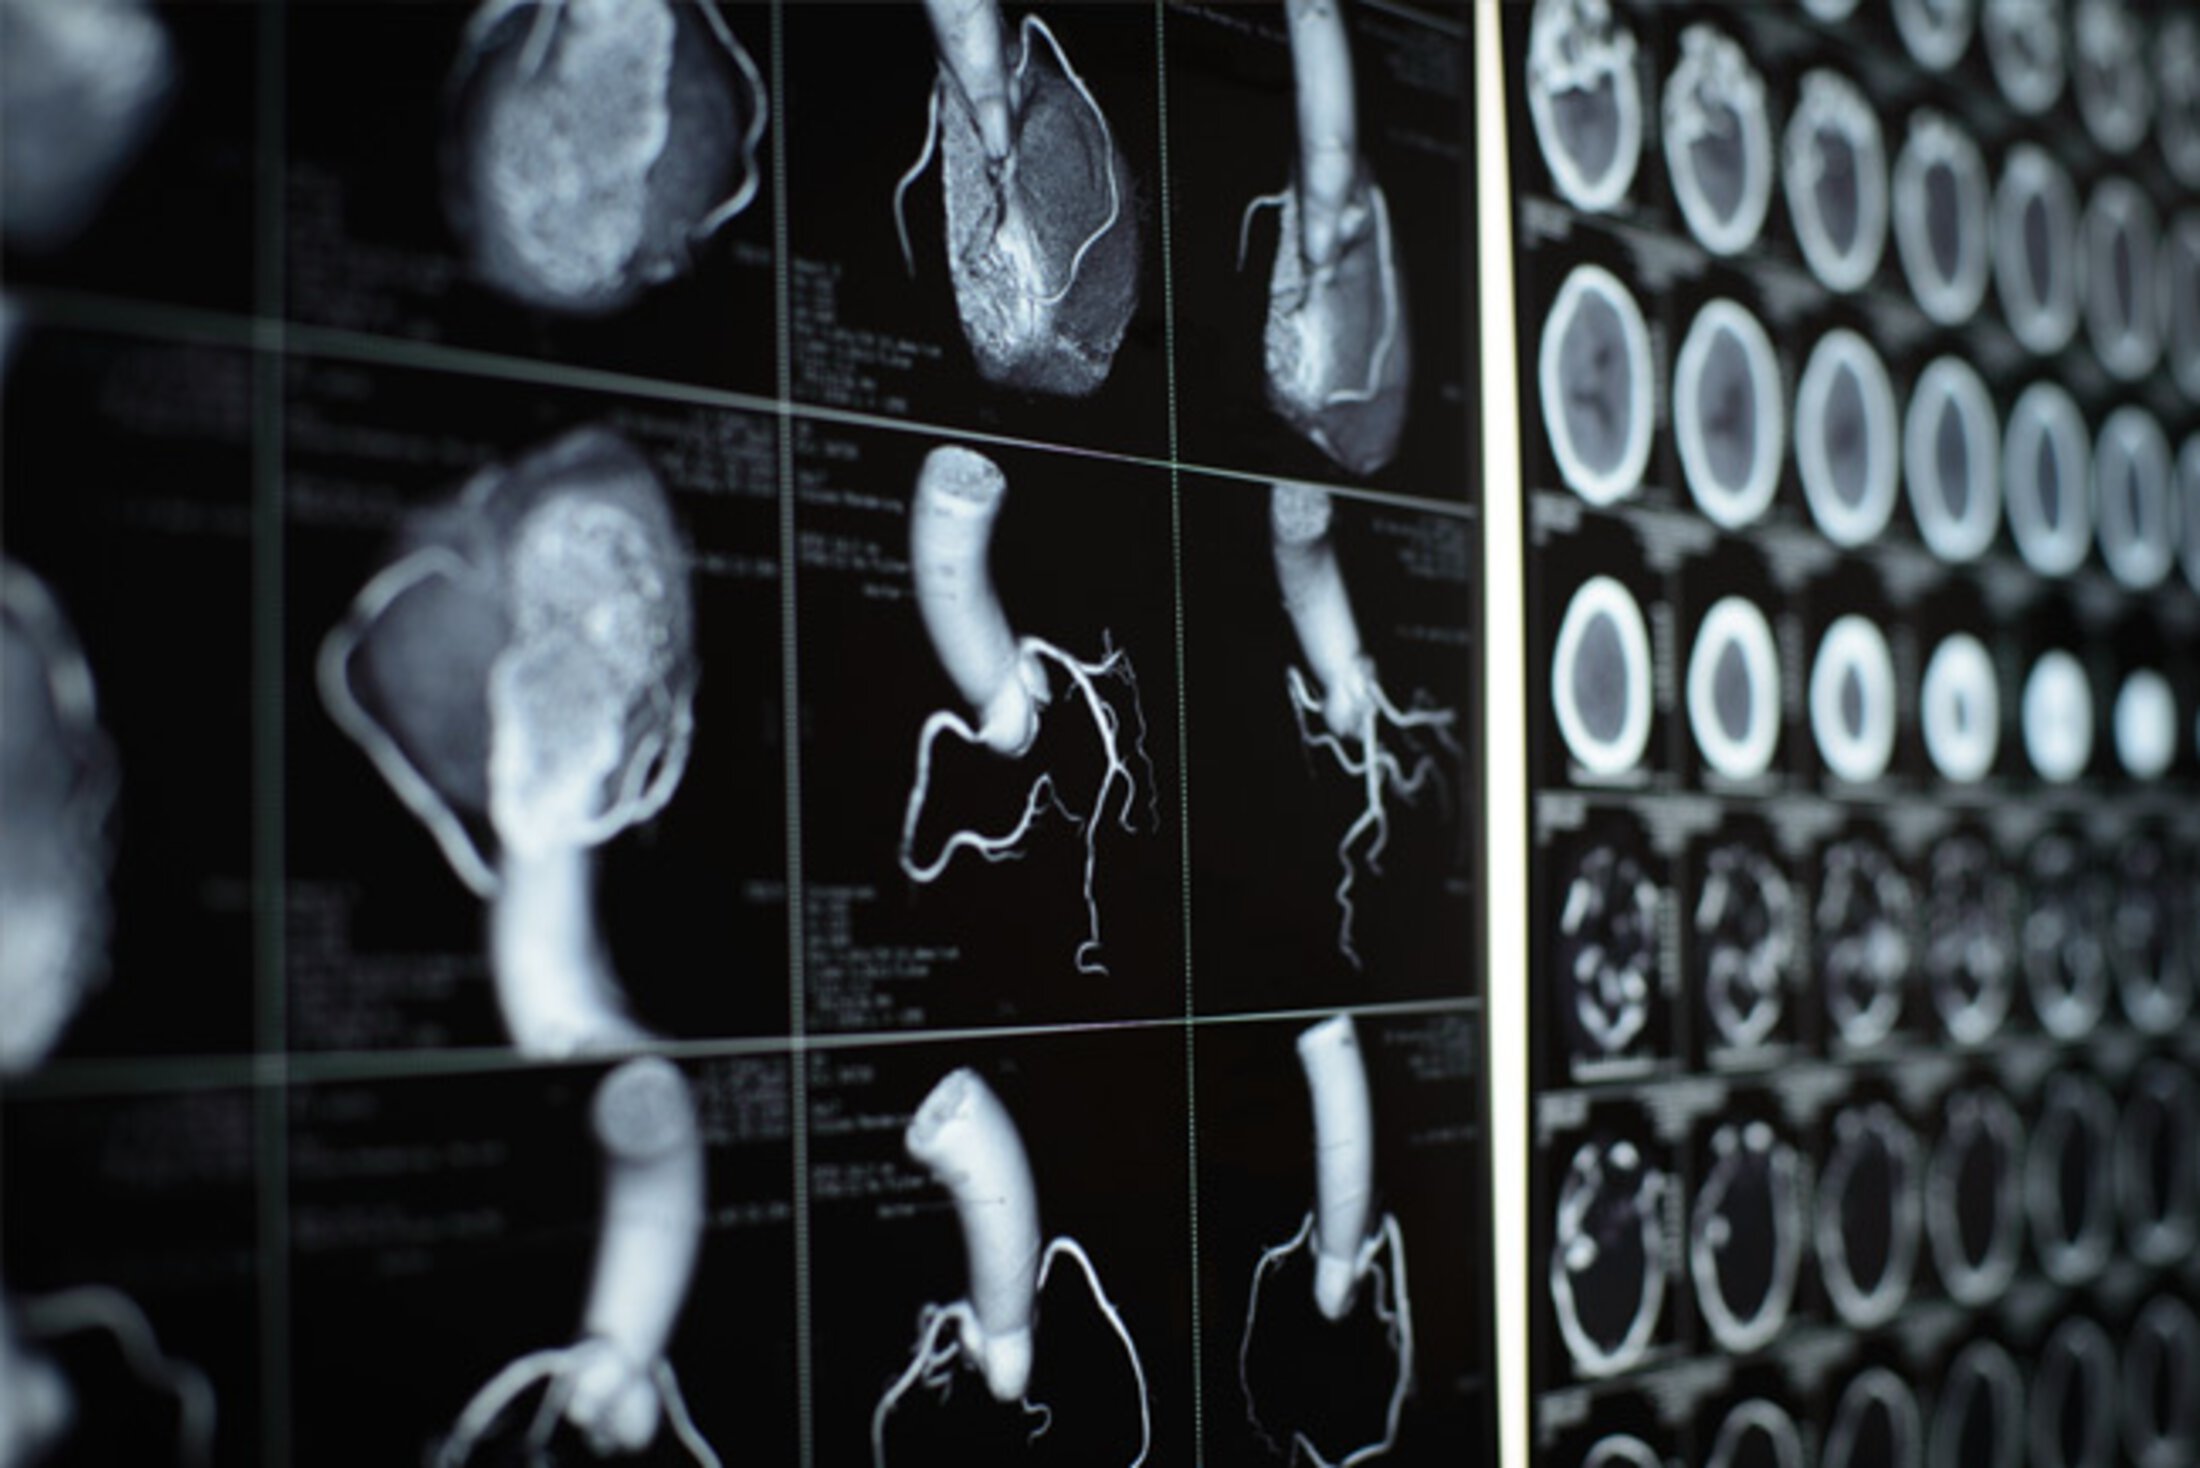

Treatment usually consists of medications, but in severe cases open-heart surgery might be required. A newer procedure known as alcohol septal ablation (ASA) helps patients avoid open-heart surgery by injecting alcohol directly into the thickened muscle via a thin catheter through either the femoral or radial artery. And patients usually feel relief immediately following the procedure.

In a more recent paper, the same research team compared the success, safety and efficacy rates of using the radial artery in the wrist versus the femoral artery from the leg to perform ASA. In the largest study on this topic to date, they found that using the radial artery was equally as effective as using the femoral artery, but cardiologists were able to use less contrast and reported fewer vascular complications. Patients also reported greater comfort and ability to walk when compared to using the femoral artery.